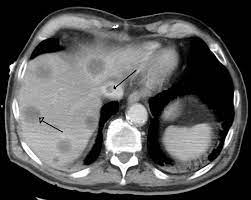

Chiasmata -mə-tə or chiasmas also chiasms 1. Esophageal varices are extremely dilated sub-mucosal veins in the lower third of the esophagus. Located in metro Denver northern Colorado and western Nebraska serving all of the Front Range our team consists of board-certified and fellowship-trained interventional radiologists. This results in hepatic congestion similar to Budd-Chiari syndrome and post-sinusoidal portal hypertension. The patients condition should be monitored throughout the procedure. They are most often a consequence of portal hypertension commonly due to cirrhosis. Toxic injury to liver sinusoids causes sloughing of endothelial cells that embolize to hepatic venules and cause eventual fibrosis of the venules. Coin in the Esophagus. There is no clear consensus regarding the number of occluded veins some authors claim that there should be at least one occluded hepatic vein 7 others state that there are no significant.

Carcinoma of the Colon. Budd-Chiari syndrome a blockage in one or more veins that carry blood from the liver back to the heart. And coumarin skin necrosis adrenal gland hemorrhage and infarction. Toxic injury to liver sinusoids causes sloughing of endothelial cells that embolize to hepatic venules and cause eventual fibrosis of the venules. Chiari malformation CM is a structural defect in the cerebellum characterized by a downward displacement of one or both cerebellar tonsils through the foramen magnum the opening at the base of the skull. Embolism and thrombosis of. La présence dune ou plusieurs affections prothrombotiques est fréquente La prise en charge repose sur un traitement anticoagulant précoce le traitement de l.